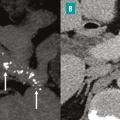

Tomodensitométrie pour identifier des lésions caractéristiques

La tomodensitométrie (TDM) est l’examen initial le plus approprié en cas de suspicion de pancréatite chronique, car elle permet d’identifier des lésions caractéristiques telles que les calcifications parenchymateuses ou des conduits pancréatiques, ainsi que l’atrophie du parenchyme pancréatique. Un protocole TDM optimal comprend des acquisitions sans injection de produit de contraste, une phase artérielle pancréatique (environ 35 à 40 secondes après l’injection) et une phase veineuse (70 à 80 secondes après l’injection). Les calcifications sont facilement détectées sous forme d’hyperdensités spontanées sur les acquisitions sans injection. Elles peuvent être de taille variable. Dans les formes avancées de pancréatite chronique, la TDM peut montrer une dilatation irrégulière du conduit pancréatique principal (fig. 2) et d’éventuelles complications, notamment les pseudokystes et les atteintes vasculaires. La TDM est en revanche moins performante dans les formes précoces de pancréatite chronique, en particulier en l’absence de calcifications. La taille et le nombre des calcifications pancréatiques doivent être évalués, car le degré de calcification dans la pancréatite chronique peut refléter l’évolution et la gravité la maladie.5 La présence de grosses calcifications constitue un signe très évocateur de pancréatite chronique. Cependant, certaines calcifications parenchymateuses pancréatiques liées au vieillissement, généralement ponctiformes (de 1 à 3 mm), ne traduisent pas nécessairement une pancréatite chronique.6